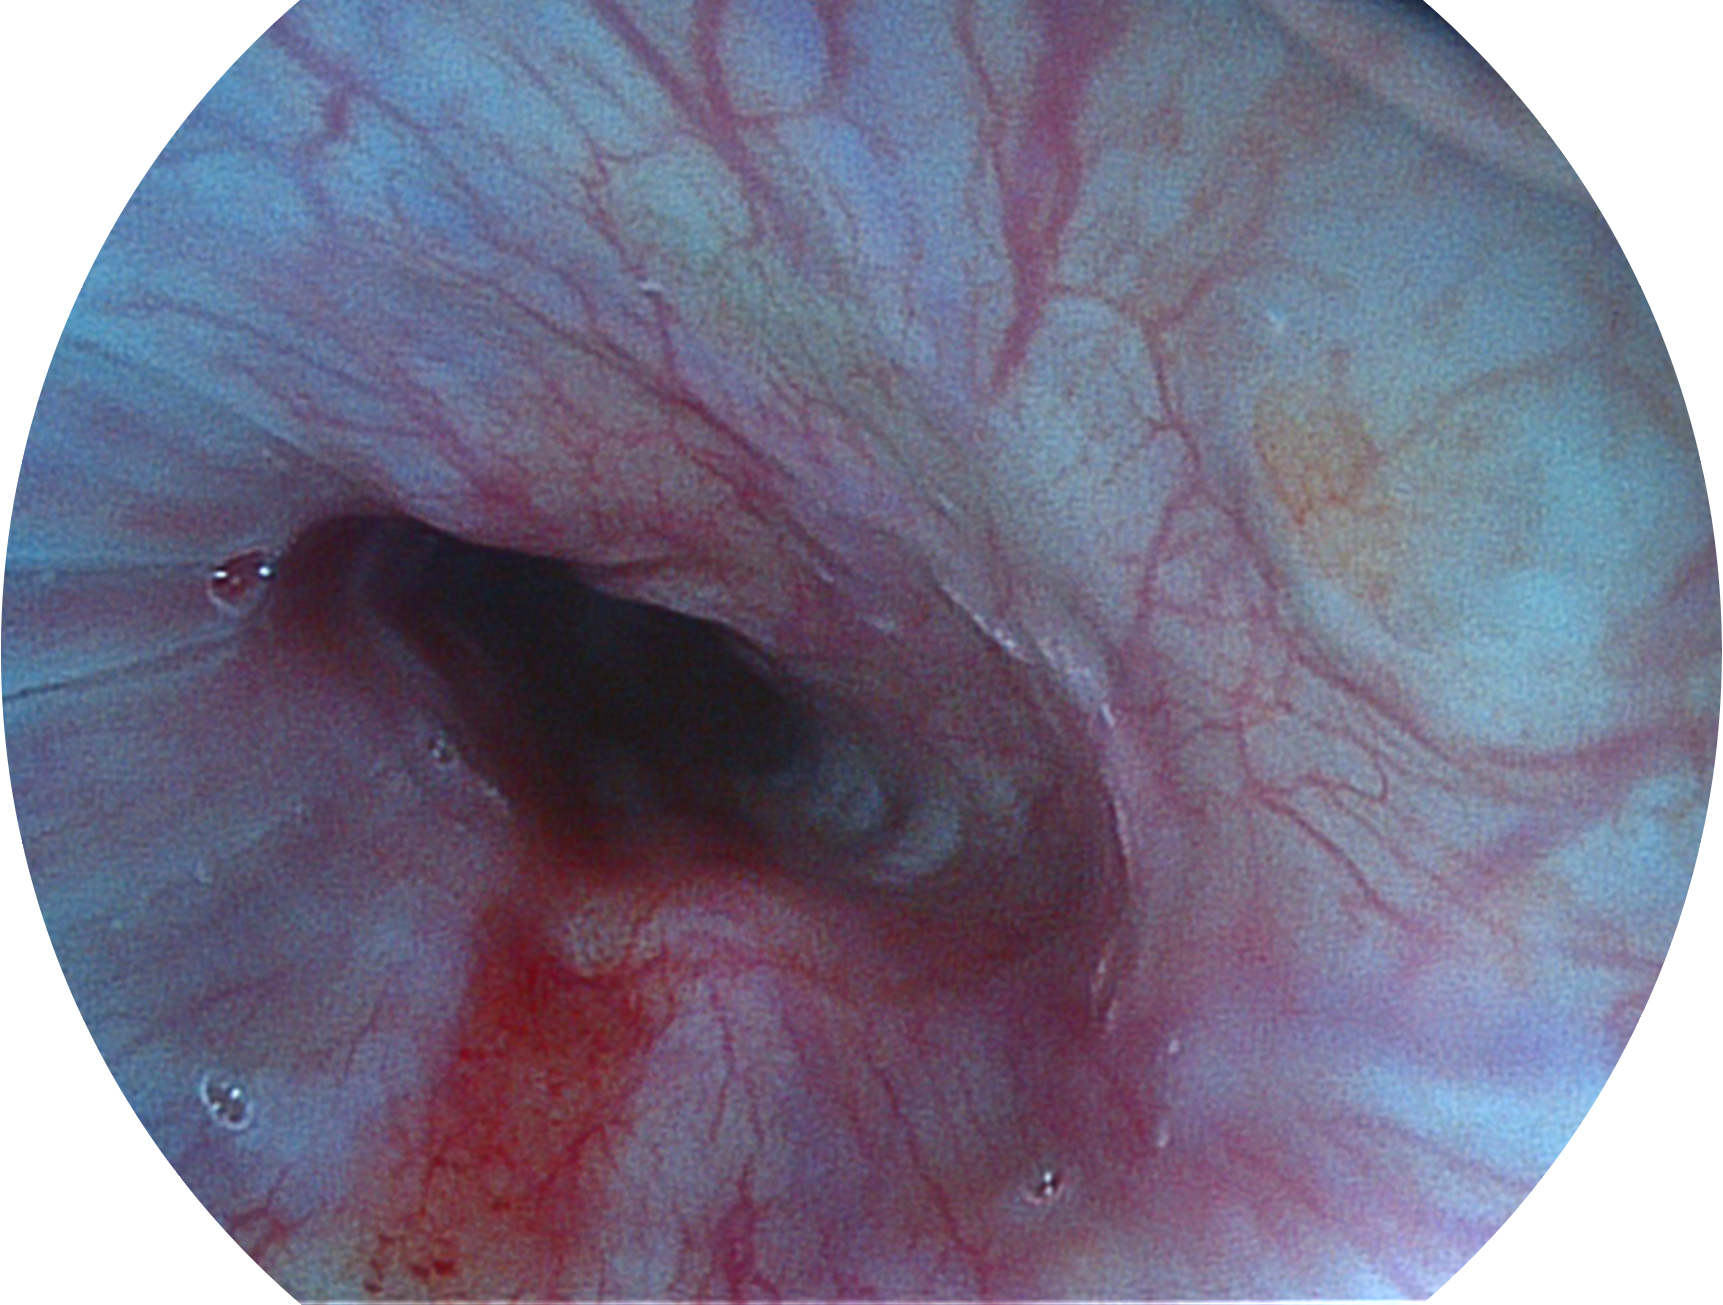

welcome海洋之神新开发的内镜染色技术,主要是基于多波长LED 光源的开发,VLS-55Q 四波长LED 光源是由四个不同颜色的LED光按照相应照明模式所规定的特定发光比例进行合束后形成,合束后形成的照明光的光谱由红光、绿光、蓝光及蓝紫光这四个不同的波段范围构成。具有更高光谱自由度,通过光谱比例的控制,实现了聚谱成像技术,英文全称为“Spectral Focused Imaging, SFI”,缩写为“SFI”和光电复合染色成像技术,英文全称为“Versatile Intelligent Staining Technology, VIST”,缩写为“VIST”。